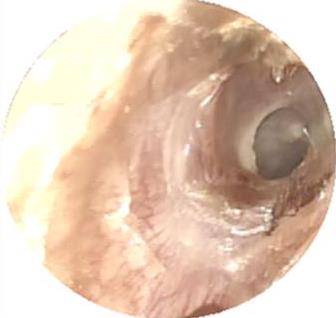

• 医用生物蛋白胶应用于耳内镜下鼓膜修补术的临床疗效

摘要:目的 分析医用生物蛋白胶应用于耳内镜下鼓膜修补术的临床疗效。方法 回顾性分析2022年10月-2023年10月该院收治的60例单纯鼓膜穿孔患者的临床资料,根据手术方法不同,将患者分为研究组和对照组,各30例。研究组术中使用医用生物蛋白胶粘合残余鼓膜和修补材料;对照组术中采用明胶海绵覆盖修补鼓膜。观察两组患者术后的鼓膜愈合情况(鼓膜愈合率、愈合时间、干耳时间和外耳道上下径)和并发症发生情况;于手术前后,采用纯音测听法(500、1 000、2 000、4 000 Hz),测量两组患者气导阈值,观察听力改善程度;采用视觉模拟评分法(VAS)评分,评估患者术后疼痛程度。结果 两组患者术后鼓膜愈合率、愈合时间、外耳道上下径和并发症发生率比较,差异均无统计学意义(P > 0.05)。研究组术后平均气导听阈明显低于对照组,差异有统计学意义(P < 0.05)。研究组术后干耳时间短于对照组,术后第1天疼痛VAS评分明显低于对照组,差异均有统计学意义(P < 0.05)。结论 医用生物蛋白胶应用于耳内镜下鼓膜修补术,可有效地降低气导听阈,缩短干耳时间,减轻患者疼痛,且不增加并发症发生率,值得临床推广应用。